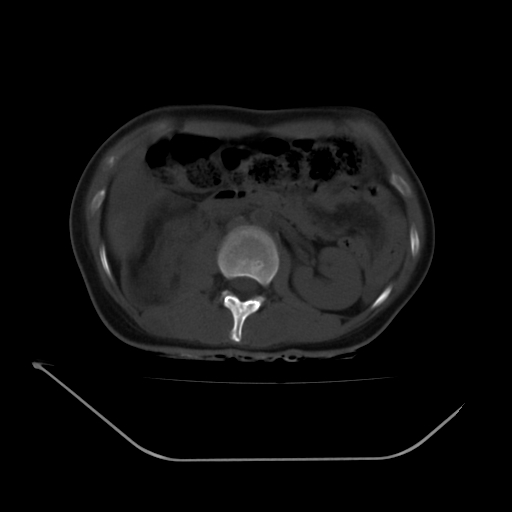

以下是引用liuyue在2008-7-19 13:02:00的发言:[br]1.肝右叶后下段及右肾挫裂伤伴腹腔积血。[br]2.右侧多发性肋骨骨折、横突骨折、右髂骨骨折伴周围软组织挫伤。[br]3.右侧腰大肌肿胀,并可见低密度影,如为气体,则肠道挫裂伤待除外。

以下是引用zhengfaming在2008-7-19 14:42:00的发言:[br]1.肝右叶后下段及右肾挫裂伤伴腹腔积血。脾脏挫裂伤待排[br]2.右侧多发性肋骨骨折、横突骨折、右髂骨骨折伴周围软组织挫伤。[br]3.右侧腰大肌肿胀,并可见低密度影,如为气体,则肠道挫裂伤待除外